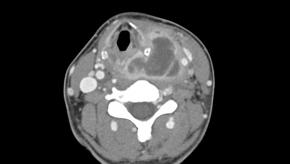

• Transverse image

Answer Infected 4th branchial cleft anomaly

Comments A Fourth branchial cleft anomaly is a rare congenital anomaly caused by incomplete obliteration of the fourth branchial pouch. It typically presents with recurrent left-sided neck infection or abscess, often involving the upper thyroid gland or adjacent neck spaces. The tract usually originates from the apex of the Pyriform sinus and extends inferiorly toward the thyroid gland, which explains the frequent association with recurrent suppurative thyroiditis. Recognition of this characteristic connection to the pyriform sinus is key to making the diagnosis.